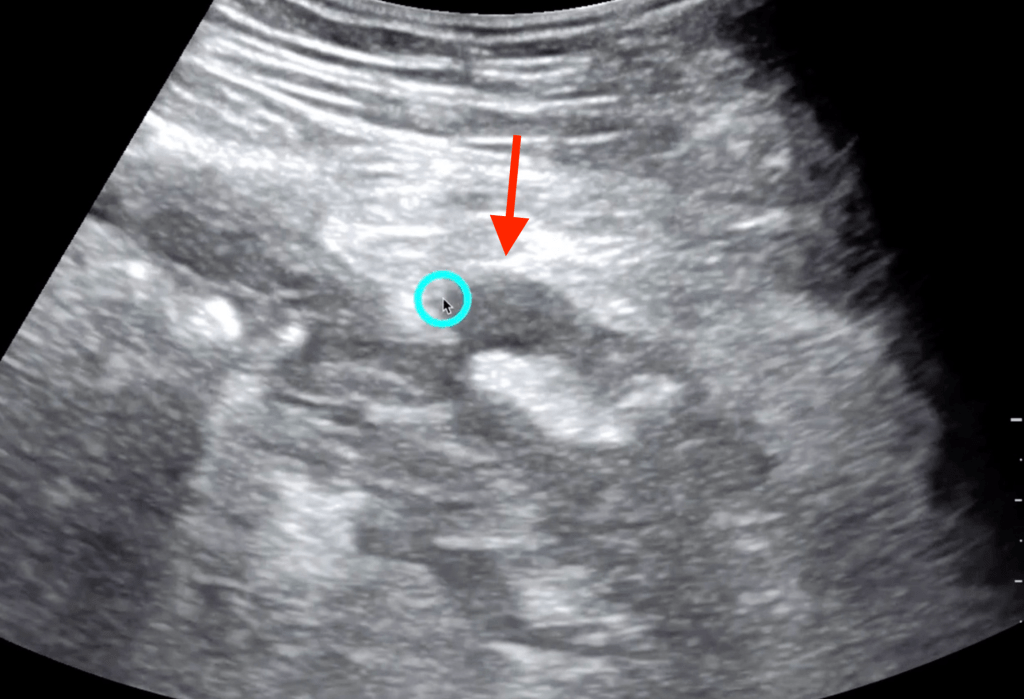

5 Minute Sono

- Large curvilinear probe

- Graded compression up and down

- Diverticula

- Bowel wall>5mm

- Prominent fluid-filled bowel loops

- Pericolic free fluid

- Increased pericolic fat (hyperechoic)

- Abscess